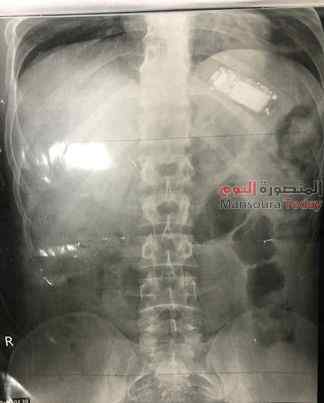

تمكن فريق طبي بمستشفى الباطنة التخصصي بجامعة المنصورة اليوم الثلاثاء 6 ديسمبر 2022 م من استخراج هاتف تليفون محمول من بطن شاب باستخدام المنظار الطبي، بعد أن ابتلع الشاب التليفون وظل بداخل المعدة لأكثر من شهرين ويعاني من آلام شديدة وفقدان للوزن، إلى أن حضر إلى المستشفى وتمكن فريق طبي من استخراج التليفون. وأكدت الدكتورة أسماء جميل مدرس بقسم الكبد والجهاز الهضمي والمناظير جامعة المنصورة، أن الشاب يبلغ من العمر 23 عاما، وقد ابتلع التليفون ولم يتمكن من استخراجه لان التليفون كان كبير الحجم، وظل داخل المعدة، ووصل إلى مستشفى الباطنة التخصصي بجامعة المنصورة، وأخبر الأطباء أنه قد ابتلع هاتف محمول منذ ما يقرب من شهرين، ولم يخبر أحد حتى تزايدت آلام المعدة، وبدأ في فقدان الوزن تم إجراء الفحوصات الطبية اللازمة من أشعة وتحاليل، وتم اكتشاف وجود التليفون المحمول داخل بطن المريض. وتبين أن المريض أجريت له عدة محاولات لاستخراج التليفون في مراكز طبية خاصة إلا أنها لم تنجح، وكان منظار اليوم المحاولة الأخيرة قبل أن يتدخل الأطباء جراحيا لاستخراج التليفون. تم اتخاذ قرار استخراج التليفون تحت اشراف الاستاذ الدكتور حازم حكيم، مدير مستشفى الباطنة التخصصي ، الاستاذ الدكتور السيد عبد المقصود رئيس وحدة الكبد والمناظير ، الدكتورة سهام سيف رئيس وحدة المناظير وتشكل فريق طبي جراحي من وحدة المناظير من أطباء وتمريض، لاستخراج التليفون بالمنظار مكون من: الدكتورة أسماء جميل مدرس واستشاري الكبد والجهاز الهضمي والمناظير جامعة المنصورة، والدكتورة سهام سيف رئيس وحدة المناظير، والدكتور السيد عبد المقصود، رئيس وحدة الكبد والجهاز الهضمي، والدكتورة دينا سعد استشاري ومدرس المناظير، والدكتور أحمد شوقي والدكتورة منة سعد والدكتورة أماني حسين، مدرسين مساعدين بوحدة المناظير وطاقم التمريض مس ايمان مسعد، ياسمين علاء الدين، وفاء ربيع.